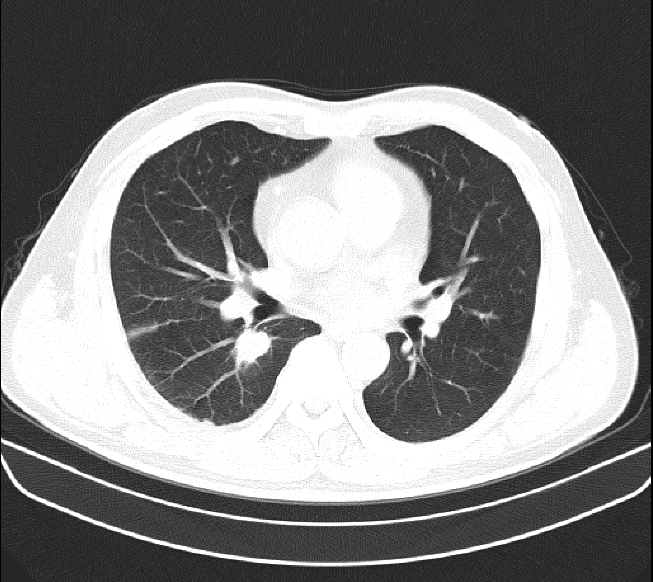

1.2차 아스트라 맞고 괜찮았는데 12/16일에 3차로 화이자 백신 맞고 다음날부터 아프기 시작하여 병원을 다니며 x-ray도 찍고 피검사도 하고 링겔도 맞고 5차례 주사 맞으며 약 먹으며 괜찮아지나 싶었는데 1/1일 20시경부터 흉통과 호흡곤란이 급격히 심해져 다니던 병원 응급실에서 CT와 각종검사결과 폐암의심 소견으로 바로 큰병원 응급실로 가서 격리실에서 통증으로 소리지르고 정신도 왔다갔다하는데 새벽에 의사 3명인가? 들어오더니 폐암이 의심된다 하더라구요~ㅠㅠ 그후 이틀간 금식하며 검사결과 상세불명의 급성폐렴,폐의농양으로 20여일간 입원후 퇴원하고 한달에 한번씩 CT찍으며 추적검사중인데 가슴이 뻐근하고 옆구리도 결리면서 호흡이 아직도 불편합니다. 주변에서는 폐는 회복이 안된다고 많이 얘기하니 답답하네요~ 병원비에 시간도 그렇고 ㅠㅠ 1/1일 CT사진 입니다.

백신 접종과 그 후유증으로 폐손상은 연관성을 찾기가 어렵습니다. 처음에 폐암으로 의심되었던 병변은 폐렴 및 폐농양으로 확인이 되었다면 일반적으로 폐농양이 다발성이거나 크지 않다면 특별한 후유증을 남기는 경우는 흔치 않습니다. 현재 CT 상에서도 폐실질이 손상되는 코로나19 감염 후 ARDS 소견과는 거리가 있어 보입니다.

현재 찍어주신 사진만으로는 정확히 알 수 없습니다.

폐 농양으로 입원하셨다면 이는 일반적으로 3~4주 이상 ( 14주까지도) 항생제 치료를 시행하며 약 5-10% 에서는 반응이 없습니다. 치료에 반응이 없으면 배액 등을 고려하며, 내과적치료에 반응이 없이 점점 커지는 농양의 경우엔 폐절제술을 시행하기도 합니다.

주어진 자료로 정확한 상태를 파악할 순 없겠으나 현재 추적관찰 CT를 촬영중인 상황으로 볼 때 급성기 치료는 어느정도 마무리 된것으로 보이며, 병원 스케줄에 따라 증상을 지켜보는 것이 좋겠습니다.